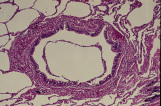

呼吸器 13. サルの肺の概観 |